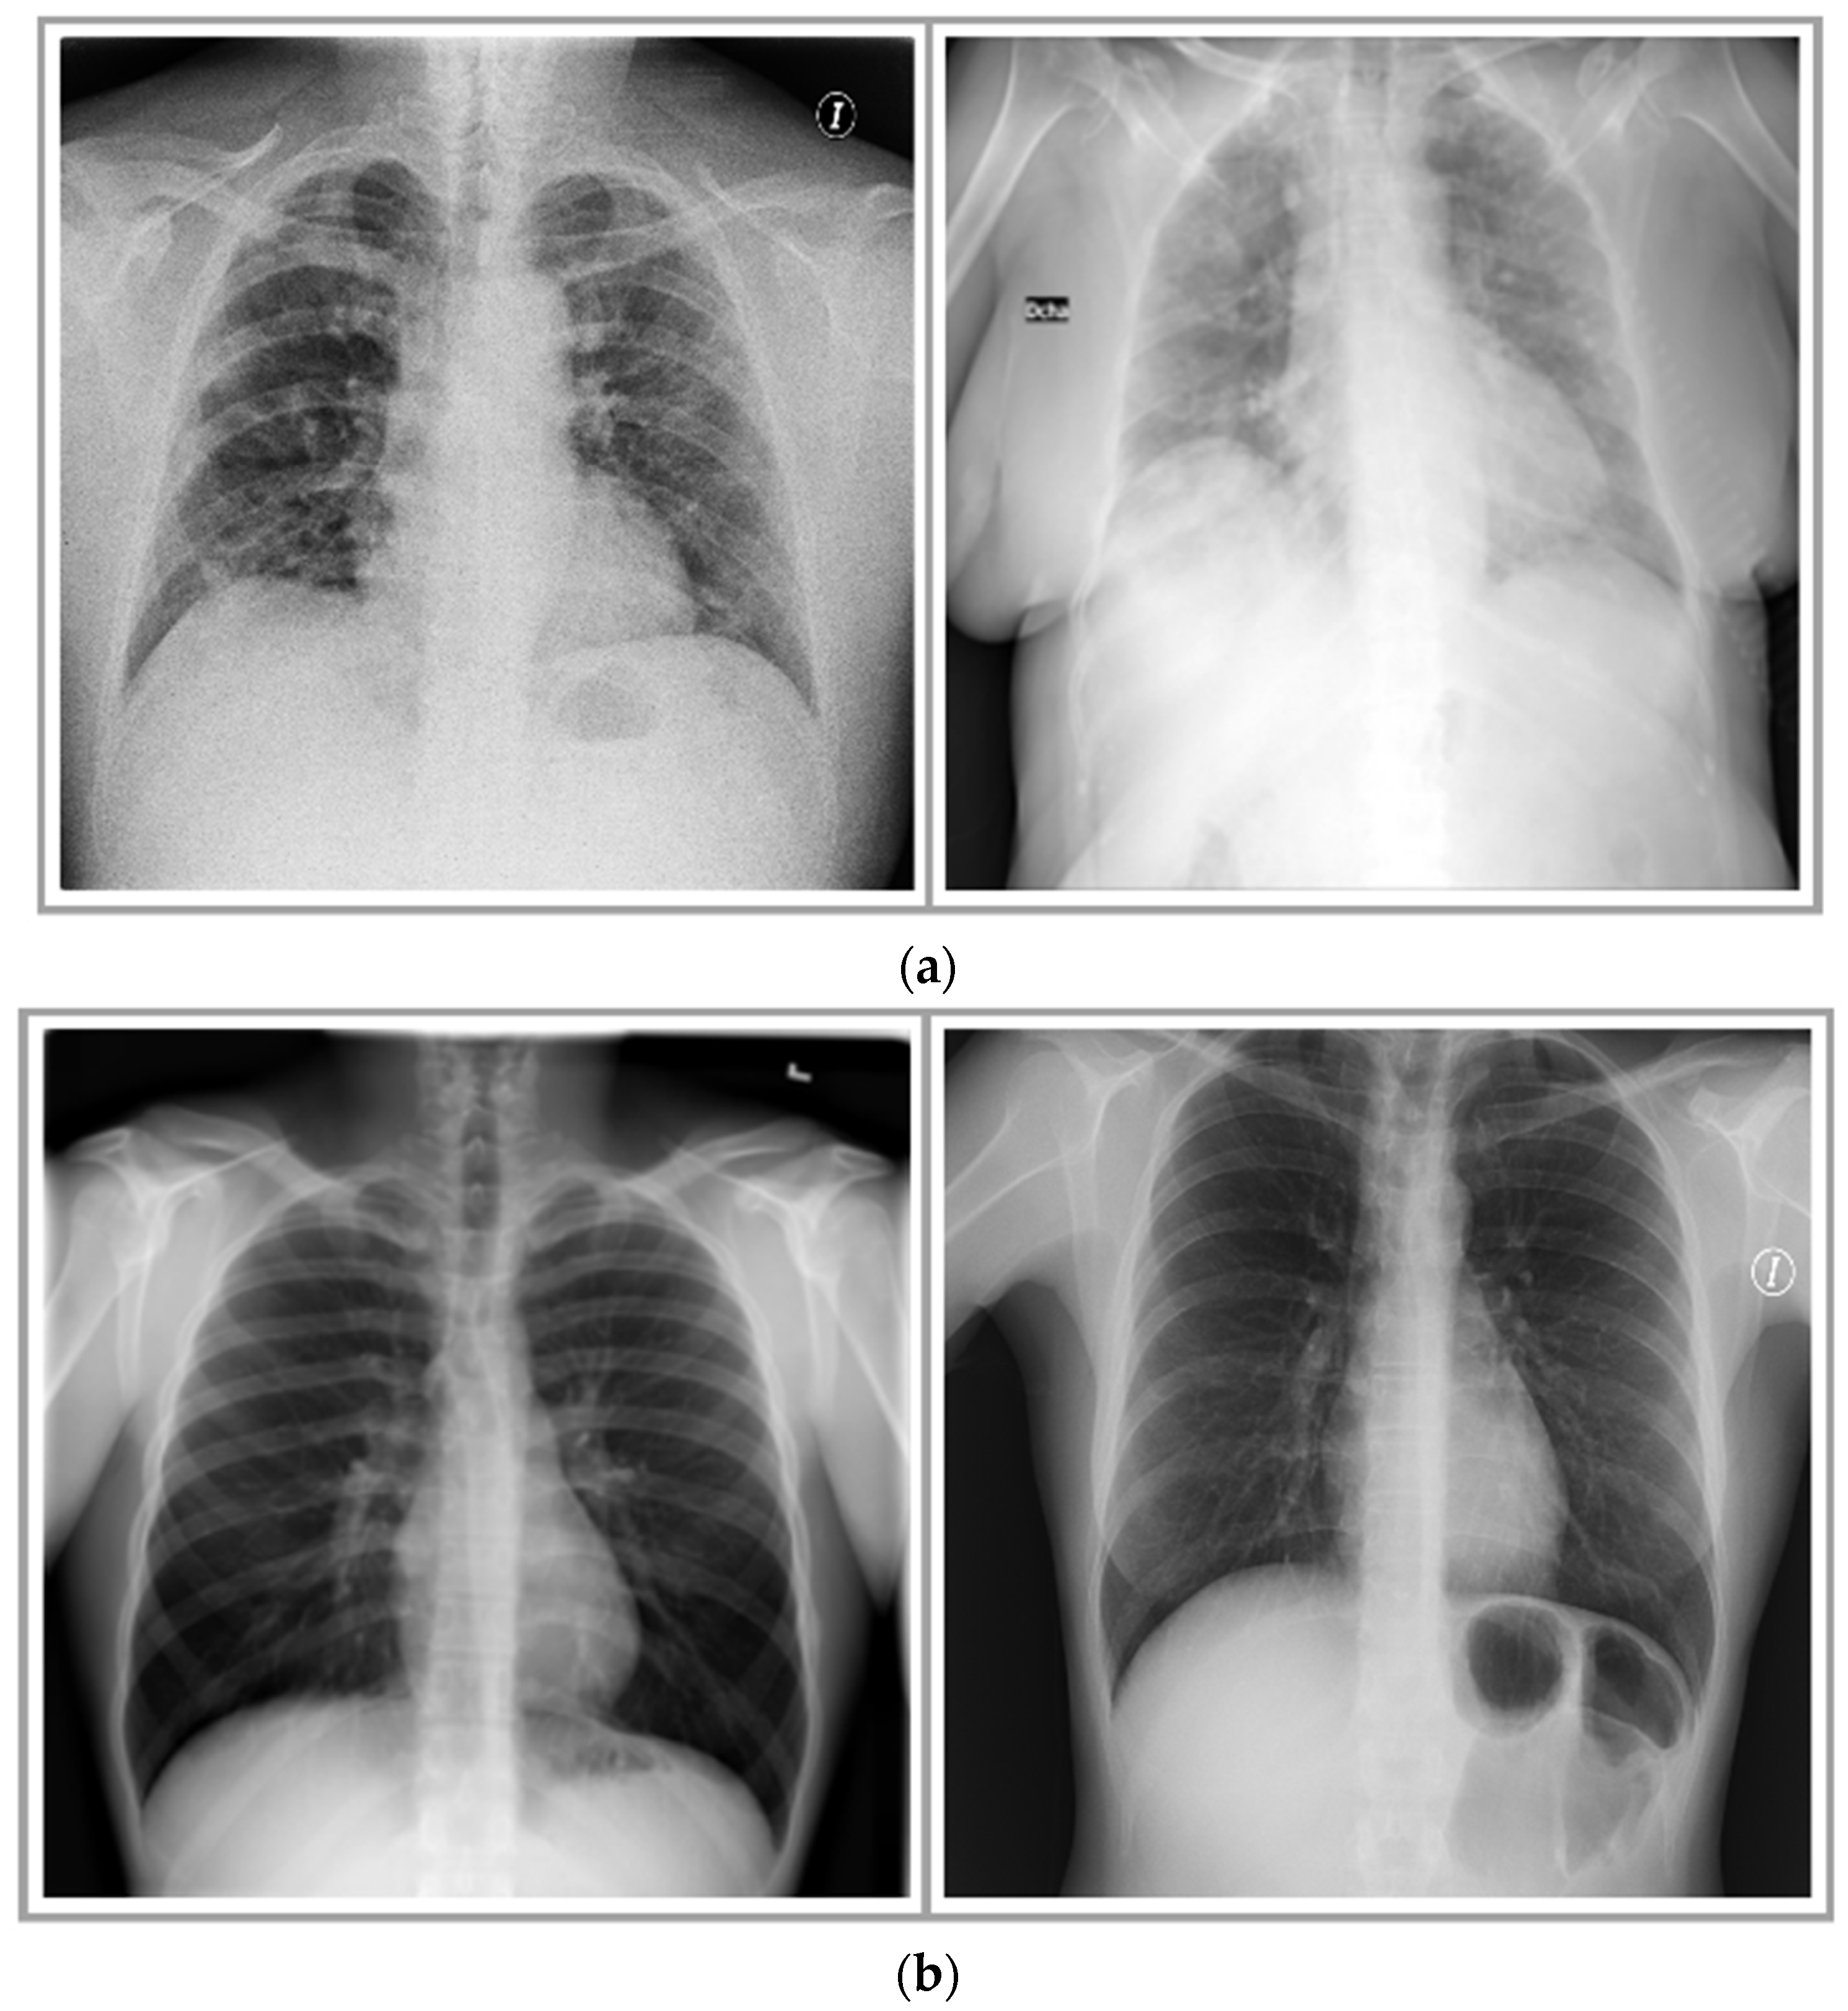

Figure 2. Sample X-ray images of the compiled dataset: (a) images of COVID-19-positive cases; (b) images of healthy individuals.

This study acquired chest X-ray images of normal, healthy individuals and COVID-19-affected patients from various publicly available online sources for training multiple machine learning classifiers and to analyze the effect of the image filtering and feature-extraction technique. The sources include: COVID-19 Radiography Database (CRD) [16] and Actualmed COVID-19 Chest X-ray Dataset Initiative (ACCDI) [17]. During the course of this experimental work, the dataset [16] contained 33,920 chest X-ray images, out of which 3616 images belonged to COVID-19-positive confirmed cases. Thus, this study accumulated 58 images of confirmed COVID-19-positive cases and 127 X-ray images of normal individuals from ACCDI and 3616 COVID-19+ X-ray images and 3547 X-ray images of normal patients from CRD, as outlined in Table 1. The radiography images taken from the dataset [16] are uniform in size (height × width: 256 × 256); however, the images present in [17] vary in size; thus, before proceeding further, this study resized these images to a fixed size (height × width: 256 × 256). Figure 2 shows few instances of X-ray images of COVID-19 cases and healthy individuals. A division of 20–80% was made in the compiled dataset as test and train sets, respectively. Moreover, 20% of the training data was further used for validation to avoid overfitting and underfitting issues.